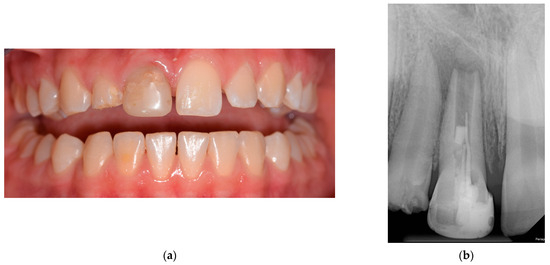

2. Detailed Case Description